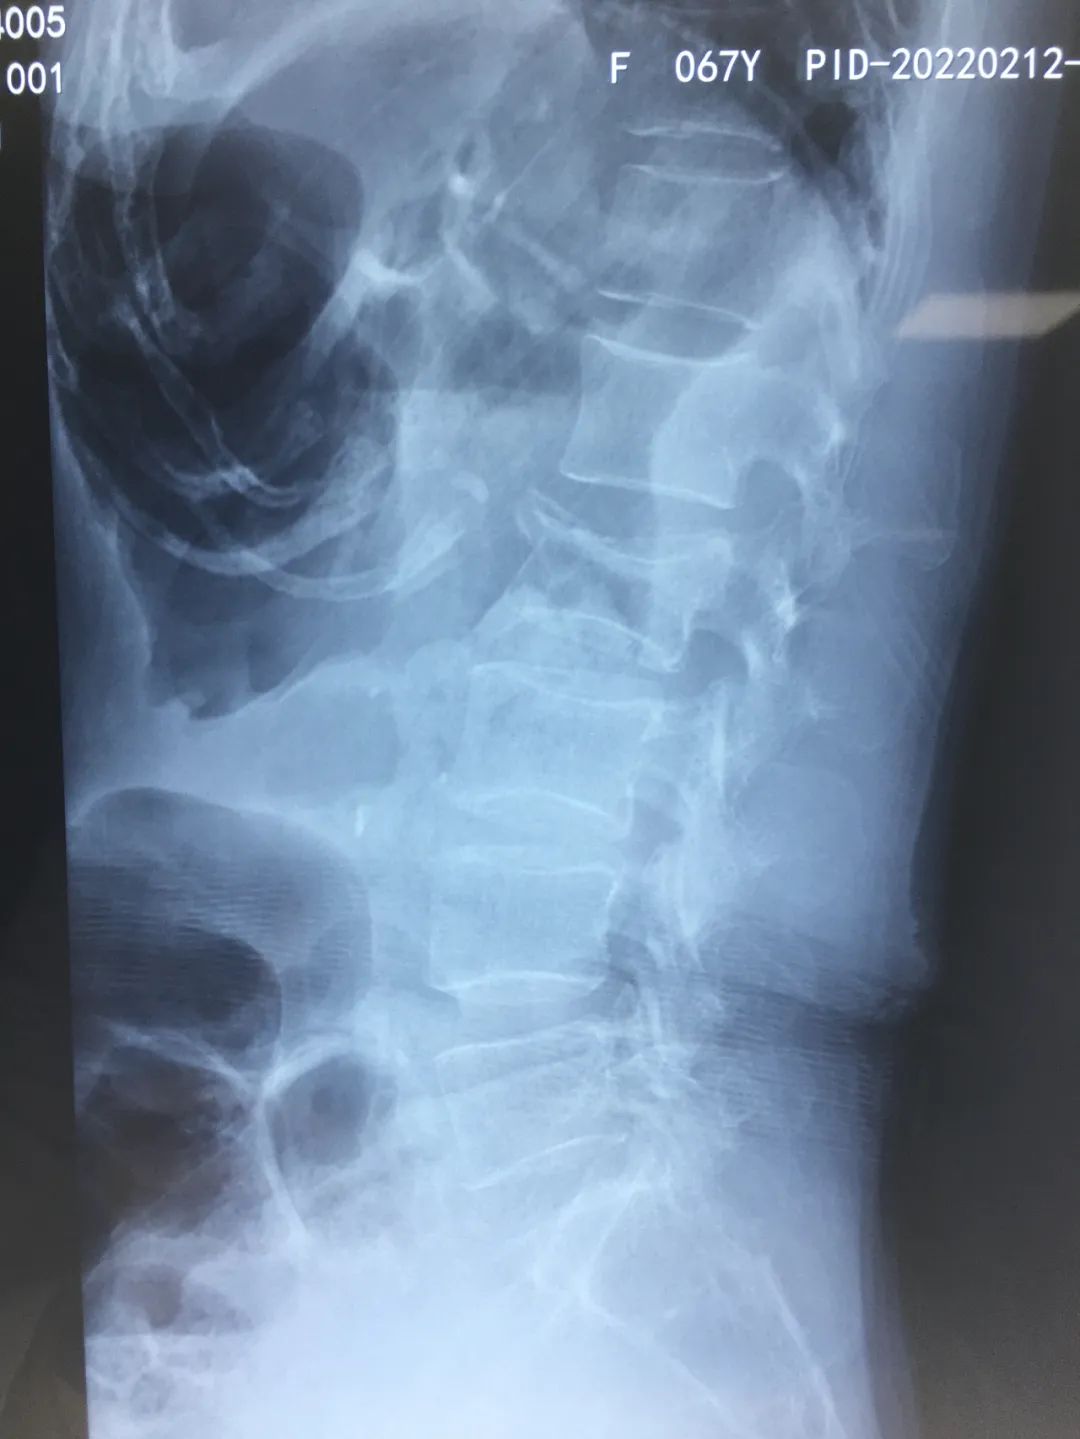

2月12日,家人将她送到陕西冶金医院就诊。医生完善相关检查,拍片提示:腰2椎体新近压缩性骨折,遂收住骨科。

检查中发现王阿姨腰2椎体新近压缩性骨折,右下腹肠管积气,麻痹性肠梗阻,特邀外科会诊。结合王阿姨情况,立即制定最佳手术治疗方案。